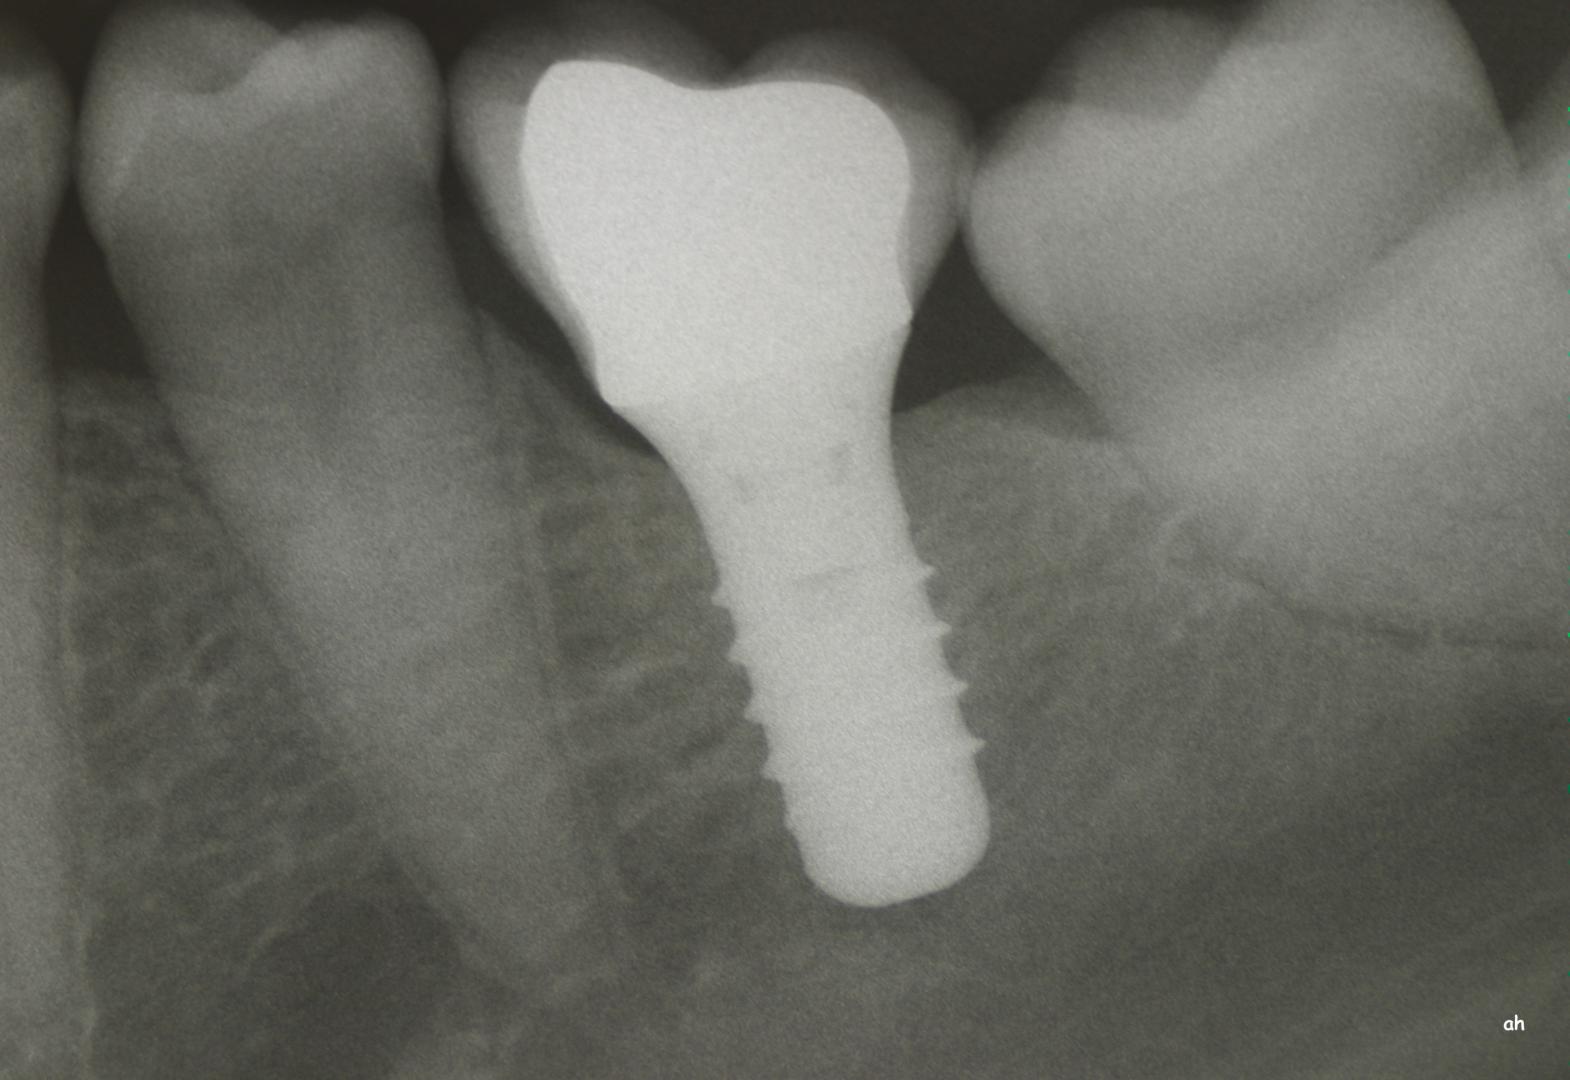

Exemple 1: Ce patient a perdu son incisive centrale gauche lors d'un accident. Un implant a été posé

Exemple 1: L'implant remplace la racine de la dent manquante

Exemple 1: L'implant s'est intégré dans l'os, une empreinte est effectuée. Le laboratoire peut réaliser la couronne en céramique.